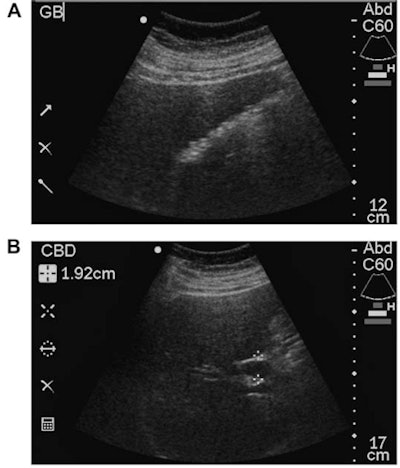

The conventional ultrasound studies were performed by sonographers certified by the American Registry for Diagnostic Medical Sonographers (ARDMS) on an HD-5000 (Philips Healthcare), IU-22 (Philips), E-8 (GE Healthcare), or Antares (Siemens Healthineers) scanner. The study's senior author, Dr. Robert Harris, read the exams immediately after they were performed; these interpretations served as the reference diagnostic standard and were confirmed or modified one year after patient enrollment based on further clinical evaluation and follow-up, laboratory/pathologic data, and additional imaging studies. Harris, who has 23 years of general ultrasound experience and 10 years of compact ultrasound experience, then performed all point-of-care ultrasound studies using a SonoSite 180 Plus scanner (Fujifilm SonoSite). The point-of-care exams were targeted, focused exams that took two to three minutes to perform.